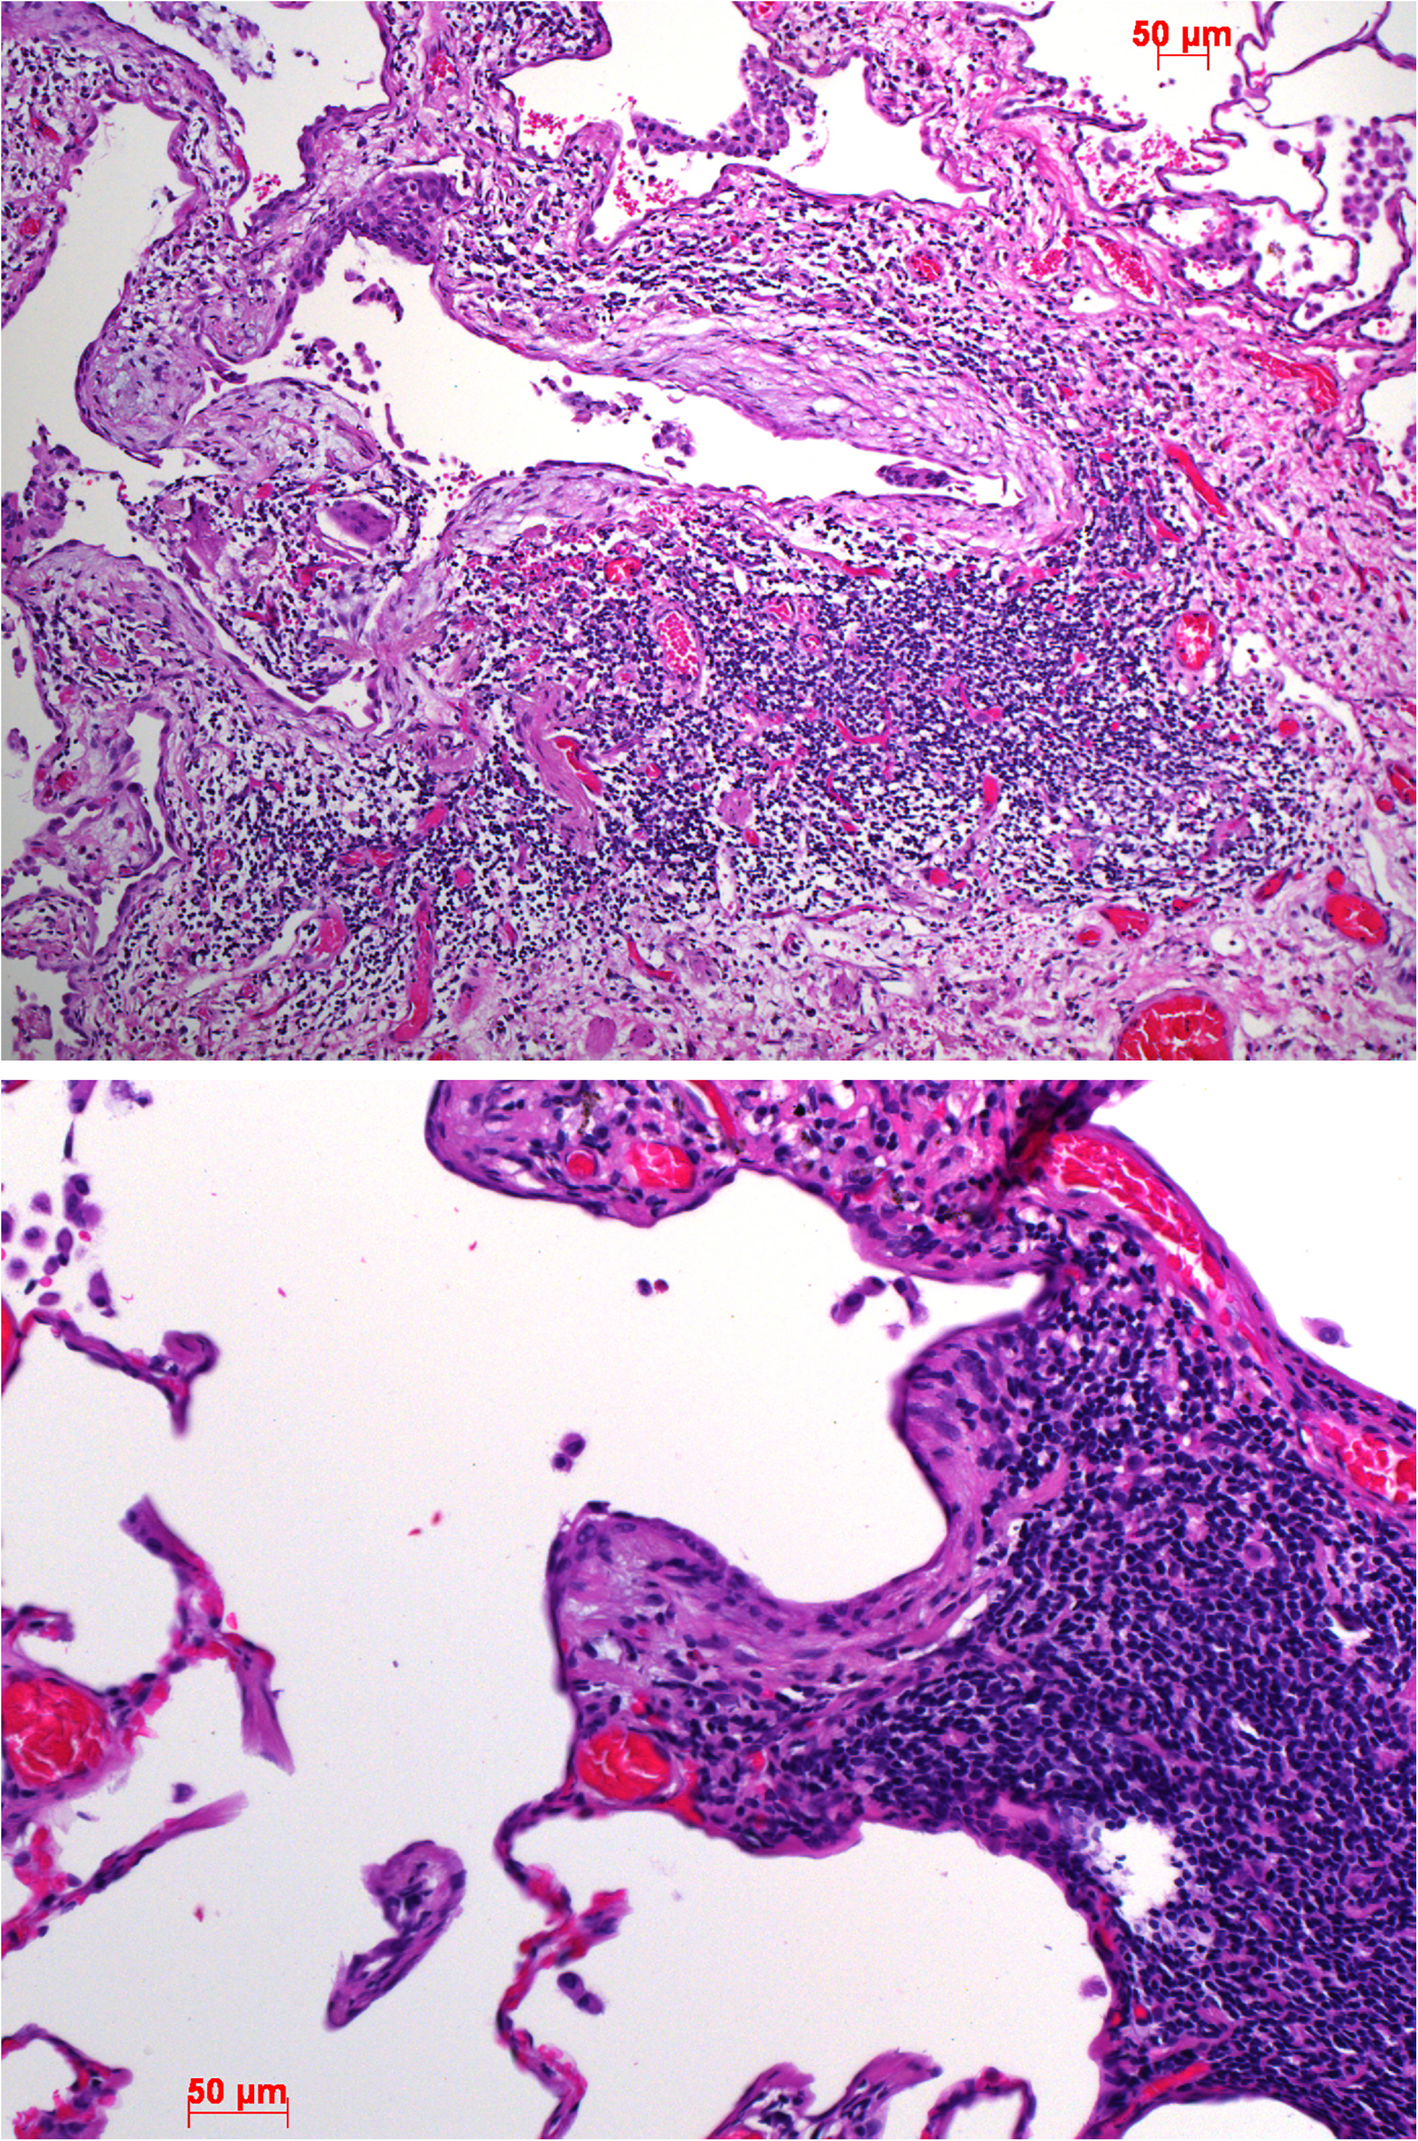

Fig. 11

Myofibroblastic foci in two cases of immune induced UIP/chronic autoimmune disease. Note the infiltration of lymphocytes in these young myofibroblastic foci. H&E, bars 50 μm